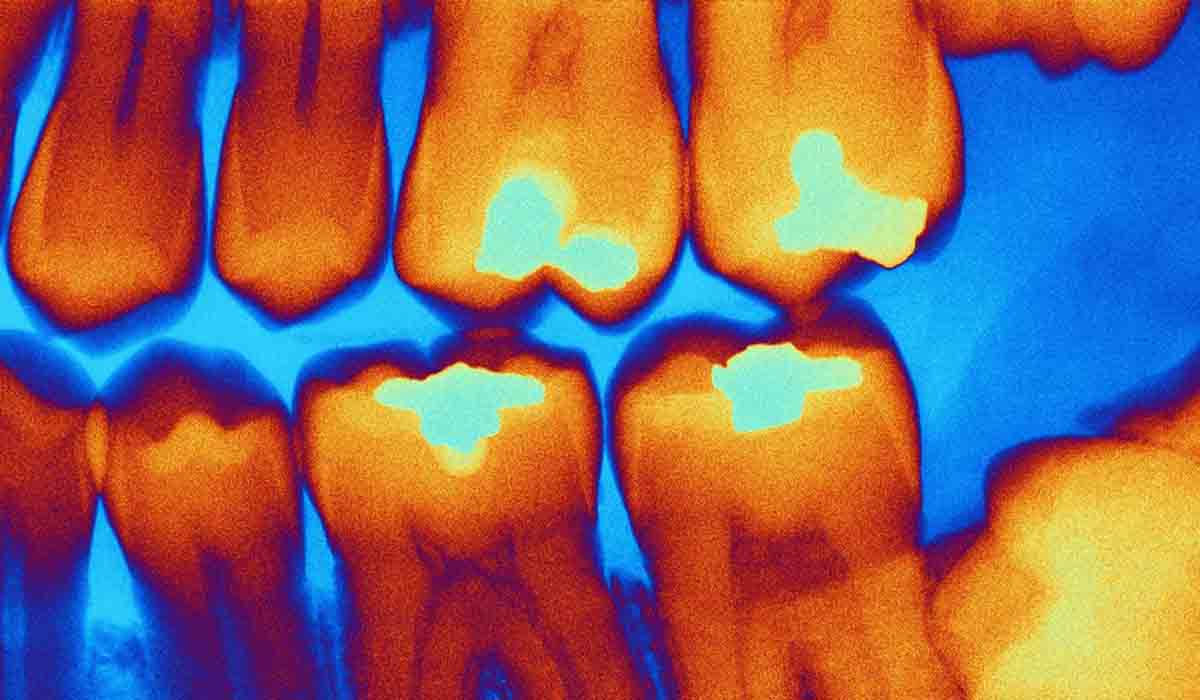

Científicos rusos crean un dispositivo capaz de diagnosticar las caries en tiempo real

El nuevo método reduce el riesgo de eliminar tejido sano y la probabilidad de complicaciones.

Imagen de ilustración. Foto: RT

Investigadores de la Universidad Sechenov de Moscú han desarrollado un nuevo dispositivo capaz diagnosticar caries durante una cita dental en tiempo real, una tarea que suele resultar difícil incluso para especialistas experimentados.

Según explicó la institución a medios locales, distinguir la dentina infectada por caries, que debe retirarse, de la dentina dañada pero aún viable, que conviene conservar, es uno de los mayores retos en el tratamiento de las caries. Aunque existen tintes especiales que ayudan a identificar el tejido afectado, estos prolongan el procedimiento y requieren pasos adicionales.

El nuevo aparato evita estos inconvenientes gracias a un método no invasivo basado en una sonda óptica que se aplica a la superficie del diente. El dispositivo registra la fluorescencia del tejido y envía la información a un ordenador, donde un modelo de aprendizaje automático determina al instante el tipo de dentina.

"Este es un enfoque fundamentalmente nuevo para la toma de decisiones clínicas", señaló Elena Nikonova, investigadora del Laboratorio de Biofotónica Clínica de la Universidad Sechenov. "Ayudamos al dentista a obtener datos objetivos directamente durante la preparación de la cavidad, lo que reduce el riesgo de eliminar tejido sano", destacó.

Los investigadores buscan ahora adaptar el algoritmo a distintos grupos de pacientes, incluidos niños, y a casos clínicos complejos. También trabajan para ampliar las capacidades del dispositivo, con el objetivo de que en el futuro pueda medir la distancia a la pulpa dental y ofrecer un control aún más preciso de la profundidad de la intervención.